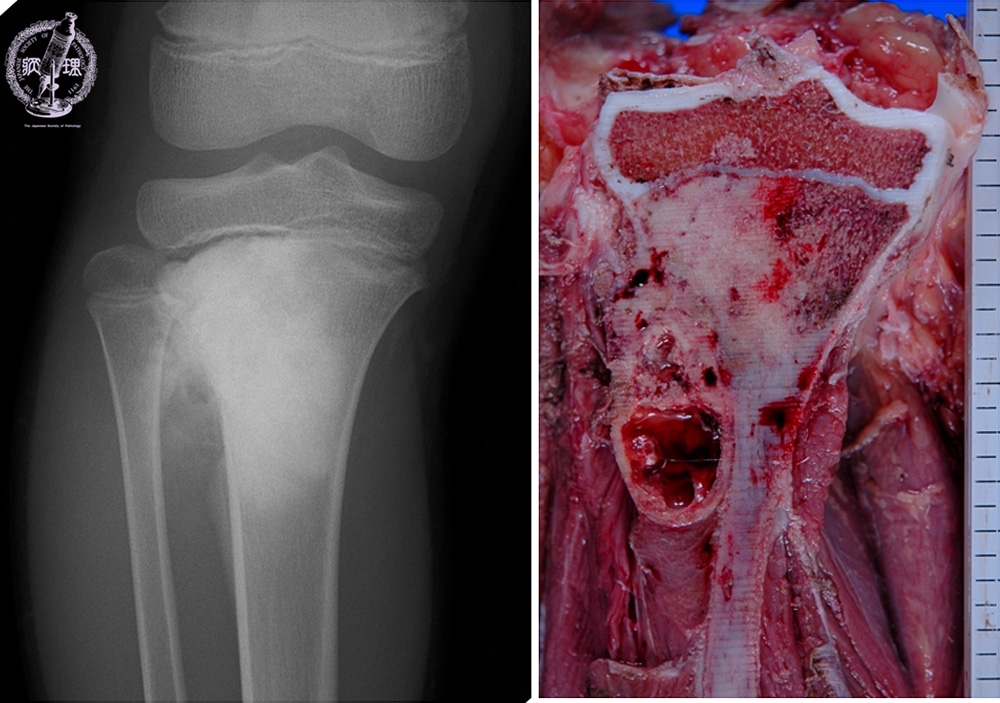

- ★(6)Osteosarcoma

X-ray finding (Left) and macroscopic view (Right): X-ray shows irregular bone destruction and sclerosis. It is concordant with macroscopic view, with destruction of cortical bone and grayish white solid tumor extending into the soft tissue.